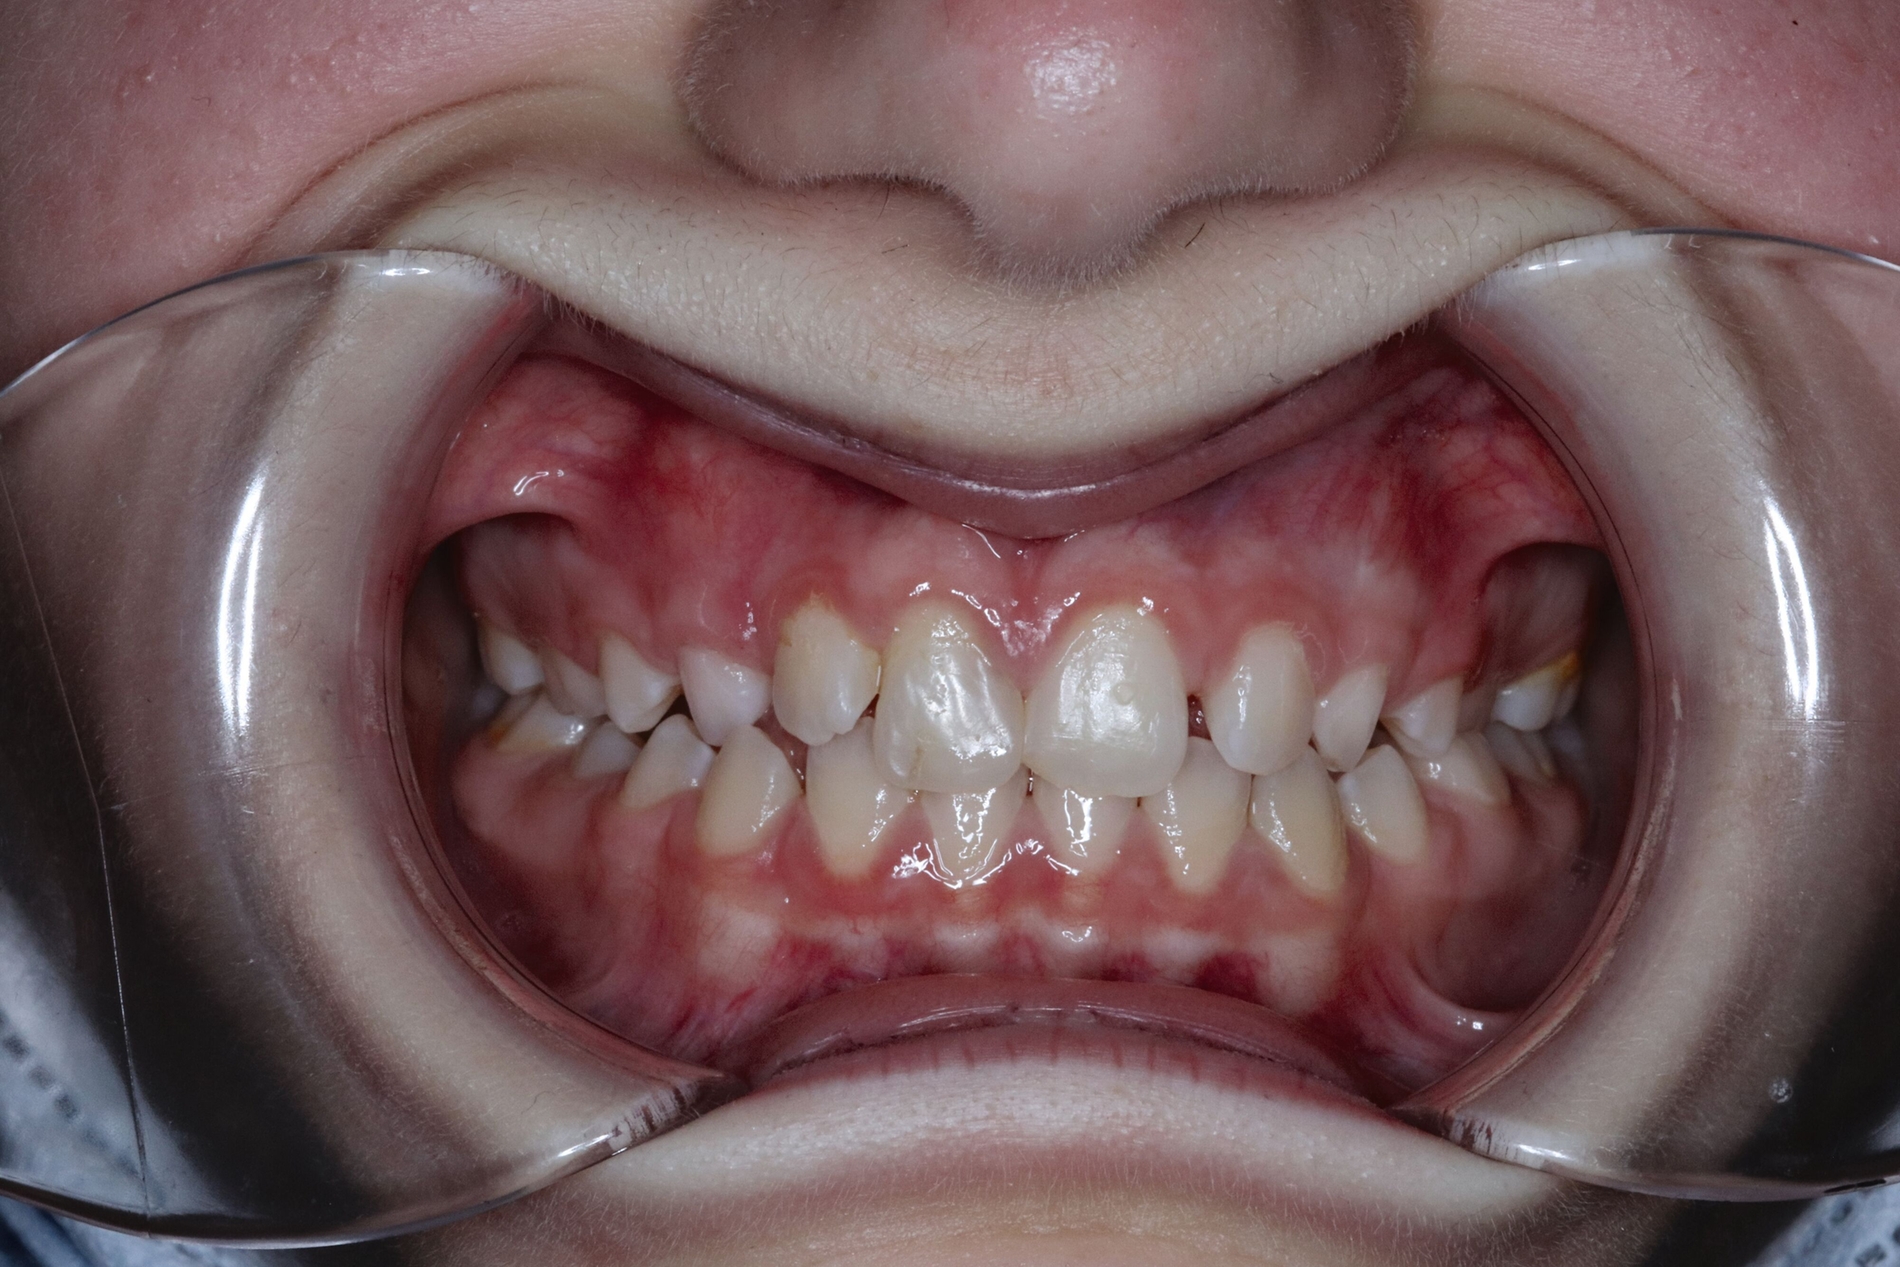

Aufgrund der infausten Prognose des replantierten Zahnes 11 entschieden wir uns für die Milchzahn-Transplantation von 83 nach 11, da dieser die längste Wurzellänge aller vier Milcheckzähne besaß. Im selben Eingriff wurde der replantierte Zahn 11 entfernt und der Milcheckzahn 83 in die Lücke 11 transplantiert. Das Transplantat wurde für drei Wochen mit einer Überknüpfnaht fixiert, die mit Kunststoff (Tetric EvoFlow®, Cavifil, Bleach XL) adhäsiv gesichert wurde (Abbildung 3a). Nach der Entfernung der Naht zeigte sich ein reizlos eingeheiltes Transplantat mit Lockerung I. Grades, negativem Perkussionstest sowie reizlosen gingivalen Verhältnissen bei einer Taschentiefe von 1 mm (Abbildung 3b).

Das Transplantat wurde acht Wochen später schrittweise in adhäsiver Technik mit Komposit aufgebaut (Abbildungen 4a und 4b) und blieb so für weitere 4,2 Jahre – funktionstüchtig – im Mund der Patientin, bis ins Alter von 13,2 Jahren. Die psychosozialen Folgen dieser sofortigen ästhetischen Rehabilitation können gerade bei Mädchen gar nicht hoch genug eingeschätzt werden.